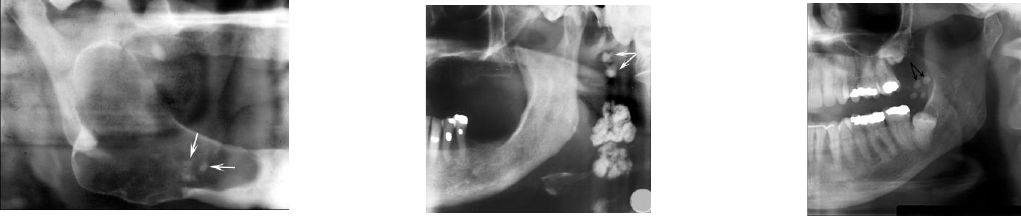

- NÓDULOS LINFÁTICOS CALCIFICADOS: ocorre em nódulos linfáticos que estão inflamados cronicamente, sendo uma

mineralização distrófica, assintomático e mais acomete submandibulares e cervicais. Pode ser provocada em casos de

tuberculose, AIDS. Não tem necessidade de tratamento em si, mas deve-se avaliar a causa. Tem característica de

formato lobulado e a deposição em cadeia.